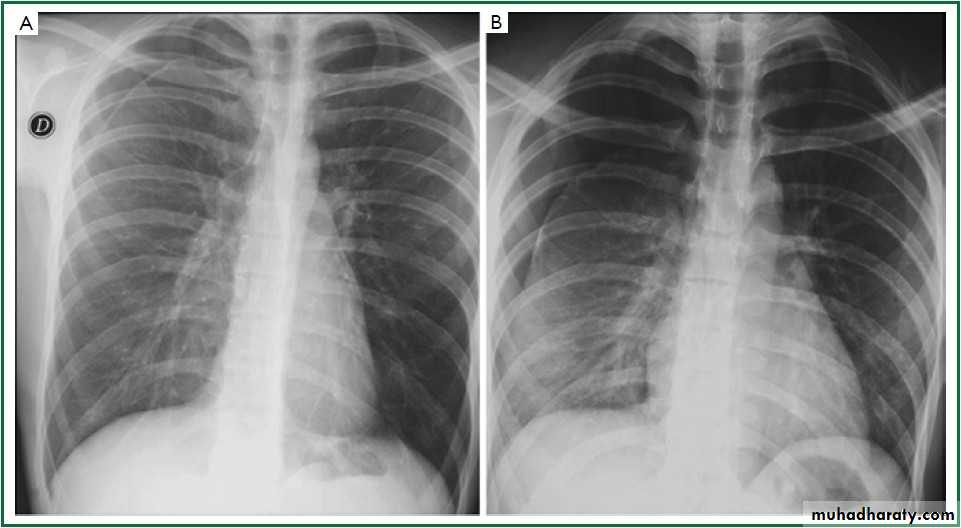

CXR:

Tension Pnenmothorax

What is the difference??Surgical Emphysema